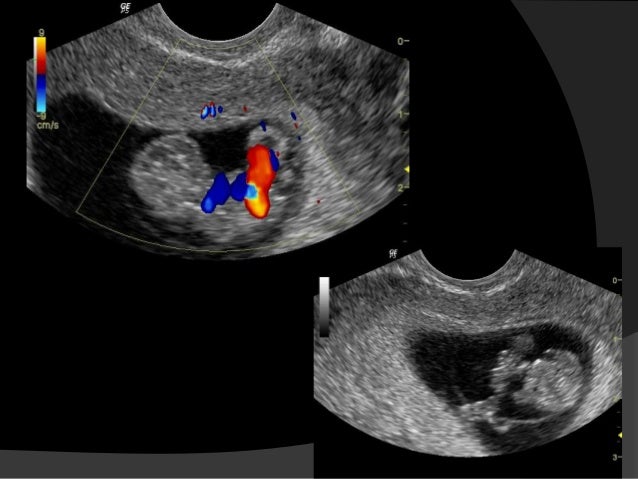

While scanning with TVS in the normal pregnancy, fetal pole/fetus was seen in 43 cases (93 .5%), whereas in comparison with TAS FP/fetus was seen in 33 cases (71 .7%) . In the abnormal pregnancy, FP/fetus was seen in 11 cases with TVS , as compared to six cases with TAS .

A TVS , also known as an internal scan , is most commonly done to confirm that you are pregnant . It's more accurate and gives clearer images than an abdominal ultrasound in early pregnancy . A transvaginal scan can: Detect the presence of the sac and/or an embryo . Find out if you're carrying more than one baby as early as the fifth week of your pregnancy .

Overall, the accuracy of sonographic dating in the first trimester is +/-5 days (95% confidence range) . Cardiac activity should be present in an embryo with a CRL β₯7 mm 3 . If it not detected at this size on transvaginal scanning performed by an experienced operator, it is an indicator of failed early pregnancy (missed miscarriage) .